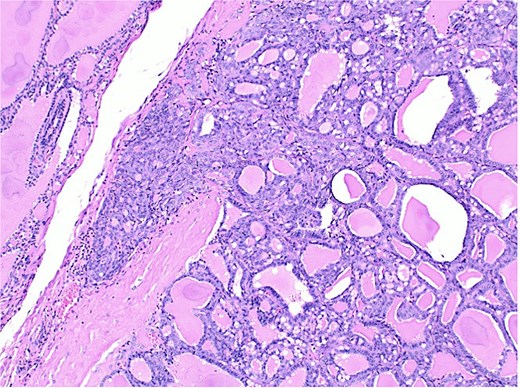

The final pathological report revealed a 1.4 cm classic papillary carcinoma in the isthmus, with extrathyroidal extension, without vascular, lymphatic, or perineural invasion, and with clear margins. In the left lobe, a minimally invasive follicular carcinoma of 3.5 cm was diagnosed, with capsular and limited vascular invasion (less than four vessels), without lymphatic or perineural invasion, and with clear margins (Figs 2–4).

Histological section of follicular carcinoma demonstrating capsular invasion through its full thickness.

Histological section showing follicular carcinoma in the upper region and papillary carcinoma in the lower region, with intervening non-neoplastic thyroid tissue.